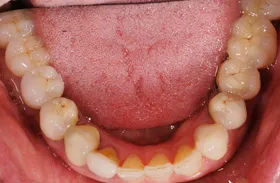

インプラントでの臼歯のかみ合わせの不調和改善例

■治療前

全ての歯の高さが、波を打ったような状態になって、咬み合わせが難しくなっています。

■治療後

術前にあった、歯の高さの不調和の問題が改善できています。

| 主訴 | かみ合わせが悪くかみにくい・時々顎関節症による痛みがある |

| 治療方法 | 補綴治療(波打ったような歯の高さを平面になるように揃えてかみやすくした) |

| 治療期間 | 約1年 |

| 通院回数等 | 約20回 |

| 費用 | 約400万円 |

| リスク・副作用 | 補綴物が過度な力で破損するリスクがある |